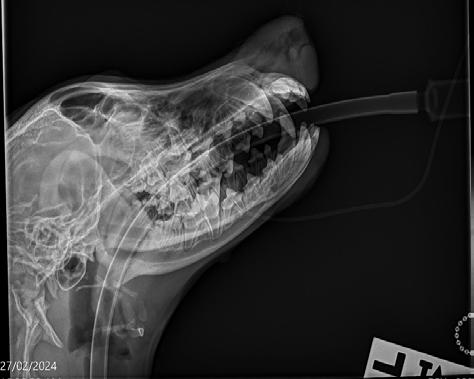

Radiographs (Figure 2) were performed of the nose and possibly some atrophy of the nasal turbinates could be appreciated; however, it was not extensive. Richard Malik noted for ‘next time’ the best radiographic view to perform is an open mouth with the X-ray plate placed into the mouth as far as it will go. Alternatively, CT would offer superior imaging and could be considered if wanting to explore the extent of the destruction, for example to determine if the cribriform plate was breached or the sphenoid sinus was infected, although it was not an option in this case due to cost considerations.